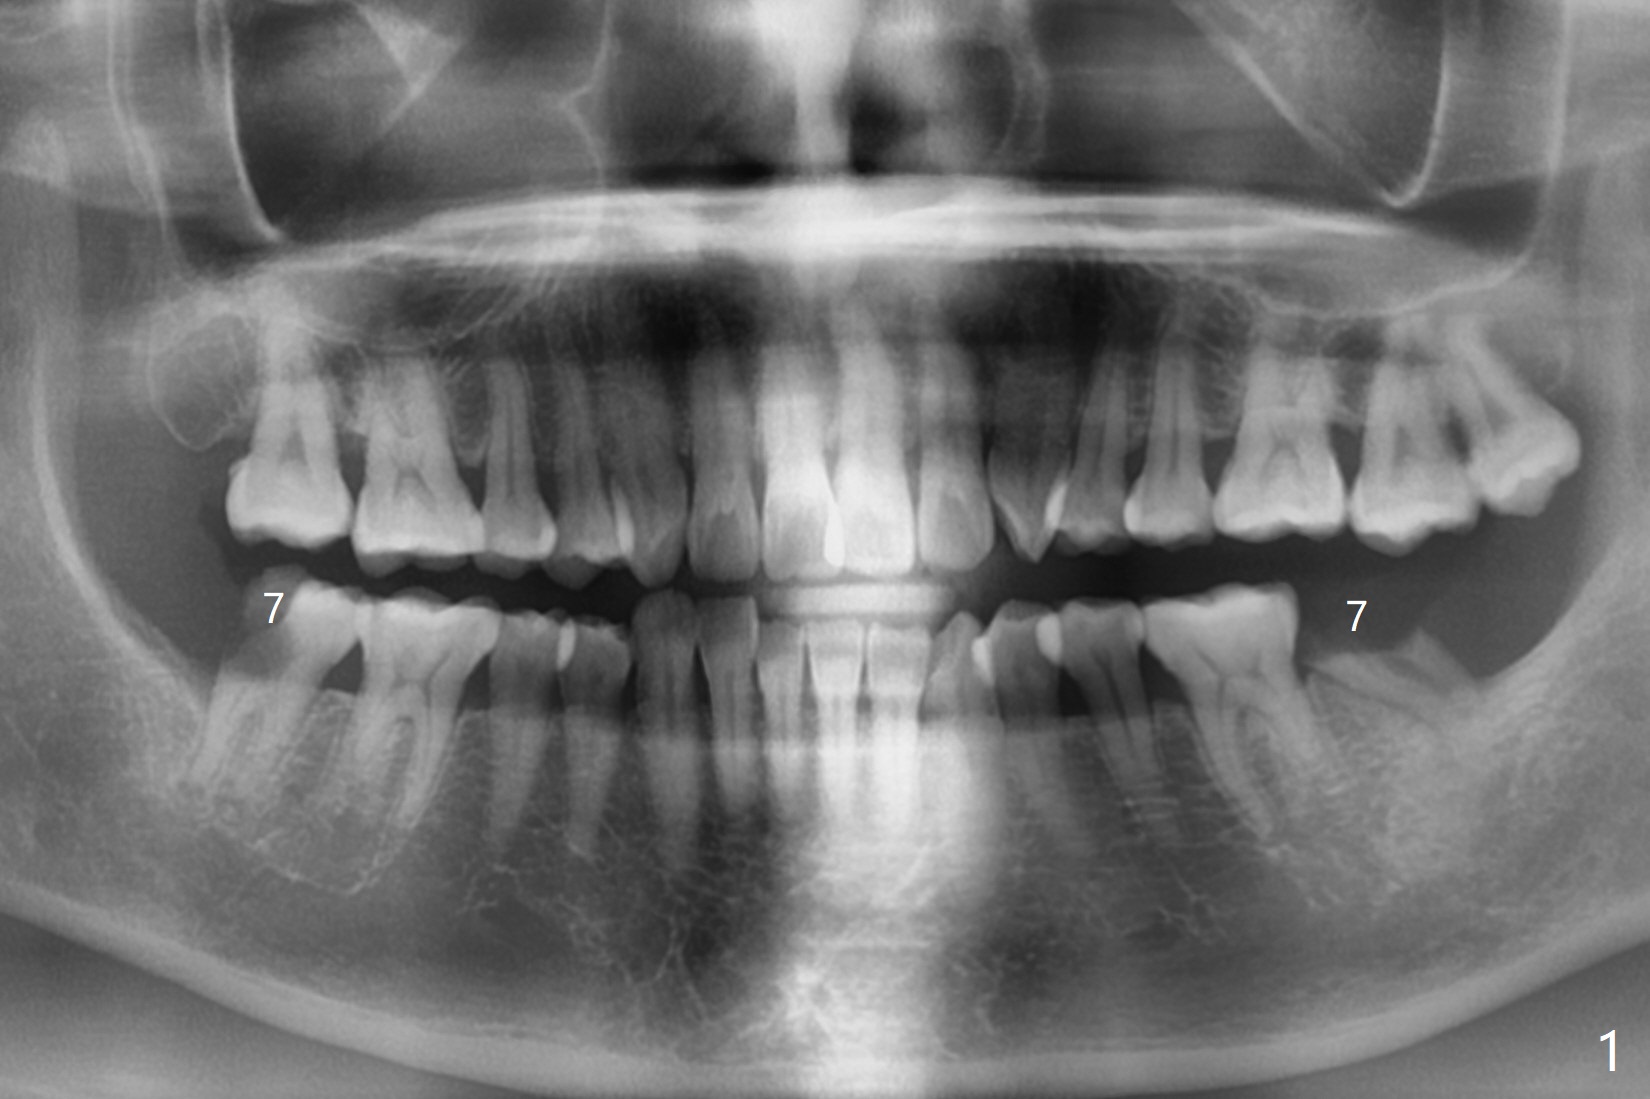

56岁女右侧不好咀嚼,右下7远中龈下龋齿(图一,二),能保留吗?Implant or rct plus crown lengthening, either way is fine, but implant may be more straightforward (Robert). Hi, Jennifer: I love the way you design implant in the mesial slope of the lower 2nd molar (Fig.1,4). When I place an implant free hand, I make sure that the long axis of the implant is 5 mm from the distal surface of the 1st molar (half of the mesiodistal width of the 2nd molar, Fig.5) as long as the implant is not too close to the neighboring root (black dashed line of Fig.5). PAs are taken several times intraoperatively to monitor the distal drifting (Fig.6 open arrow) of the osteotomy (red line). In my opinion, the drifting exists with guided surgery, especially the change of angulation. Can you intentionally move the implant mesially (Fig.7 open arrow) by 0.5-1 mm depending upon bone density or tilt the implant mesial coronally? Thanks for your consideration.